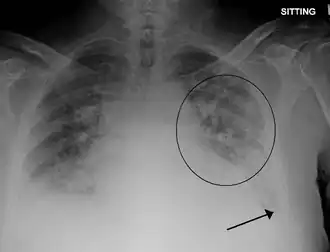

Рентгенография: линии Керли при застойной сердечной недостаточности с интерстициальным отёком лёгких, симптом «крыльев бабочки» или диффузные очагово-сливные изменения при альвеолярном отёке.